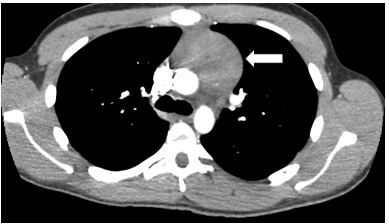

An abnormality was noted in the left mediastinum which prompted his physician to order a computed tomography (CT) of the chest and to refer him to a pulmonary specialist. This CT scan (Figures 2 and 3) revealed a rounded, well-demarcated mass in the superoanterior mediastinal compartment. The largest diameter measured 6.8 x 4.8cm.

Figure 3. Computed tomography (CT) image of the chest demonstrating well-demarcated soft tissue mass in superoanterior mediastinal mass (arrow).